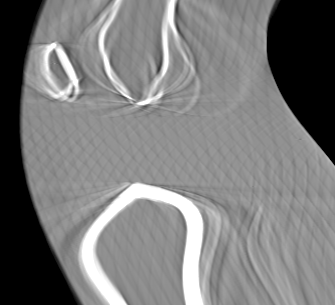

Involuntary subject motion is the main source of artifacts in weight-bearing cone-beam CT of the knee. To achieve image quality for clinical diagnosis, the motion needs to be compensated. We propose to use inertial measurement units (IMUs) attached to the leg for motion estimation. We perform a simulation study using real motion recorded with an optical tracking system. Three IMU-based correction approaches are evaluated, namely rigid motion correction, non-rigid 2D projection deformation and non-rigid 3D dynamic reconstruction. We present an initialization process based on the system geometry. With an IMU noise simulation, we investigate the applicability of the proposed methods in real applications. All proposed IMU-based approaches correct motion at least as good as a state-of-the-art marker-based approach. The structural similarity index and the root mean squared error between motion-free and motion corrected volumes are improved by 24-35% and 78-85%, respectively, compared with the uncorrected case. The noise analysis shows that the noise levels of commercially available IMUs need to be improved by a factor of $10^5$ which is currently only achieved by specialized hardware not robust enough for the application. The presented study confirms the feasibility of this novel approach and defines improvements necessary for a real application.